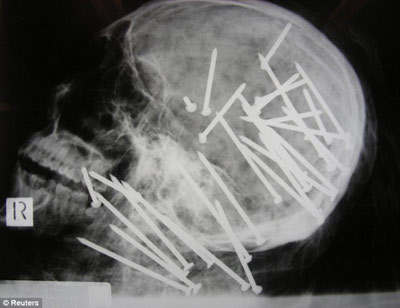

X光顯示,劉晨(音譯)頭部和頸部被釘有30枚鋼釘

據報道,該男子名叫劉晨(音譯),于2000年移民澳大利亞墨爾本市,4年后搬往悉尼。2008年11月,劉晨的男性友人向悉尼警方報案,稱其已經失蹤一段時間,警方遂展開調查。兩周后,兩名在悉尼喬治河上劃船的男孩發現了劉晨已經高度腐爛的浮尸。警方稱,當時劉晨被一條毯子緊裹著,四肢被電線捆得結結實實,警方將尸體交與法醫進行X光檢查后驚異地在他頭部和頸部發現了30枚鋼釘。

負責本案的警官馬克·紐漢表示:“尸檢結果顯示,兇手用一種無繩氣動式射釘槍對著死者的頭部和頸部開了30槍,這種標準式射釘槍哪都可以買到。”悉尼警司杰夫·貝雷斯福德告訴記者:“這起謀殺案令所有的警察震驚不已,在我36年的辦案生涯中,還從來沒見過性質如此惡劣的兇案……就是因為這起謀殺案是如此的殘忍,所以我們希望公眾能夠為警方提供更多的破案線索。”